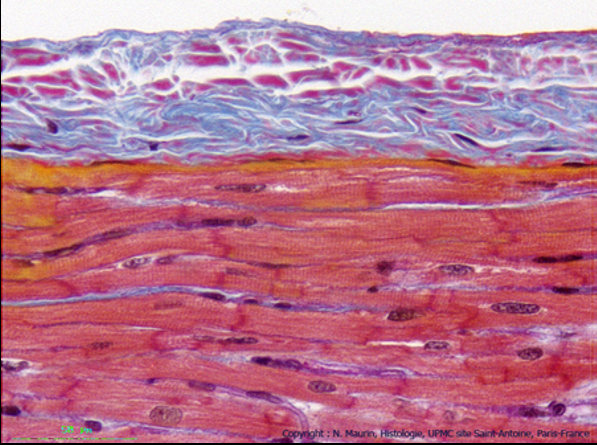

Pour cette coupe,

http://www.edu.upmc.fr/histologie/C/coe ... oeur03.htm

Déjà on remarque qu'elle est à fort grossisement (on voit très bien les striations des cellules myocardiques)

Puis, c'est pas précisé mais la coupe a été colorée au

Trichrome de Masson => donc ce que tu vois en

bleu c'est des

fibres de collagène =>

Tissu conjonctif (sous-jacent à l'épithélium => endocarde)

Enfin, souviens toi que le tissu conjonctif sous-endocardique à une épaisseur, une texture et une composition VARIABLE en fonction des régions cardiaques qu’il tapisse => cavités auriculaires, ventriculaires ou valves.